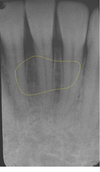

This is located palatal to incisors, pear-shaped opening; nasopalatine nerves and vessels

incisive foramen

This leads to the incisive foramen; radioopaque margins, radiolucent center

incisive canal